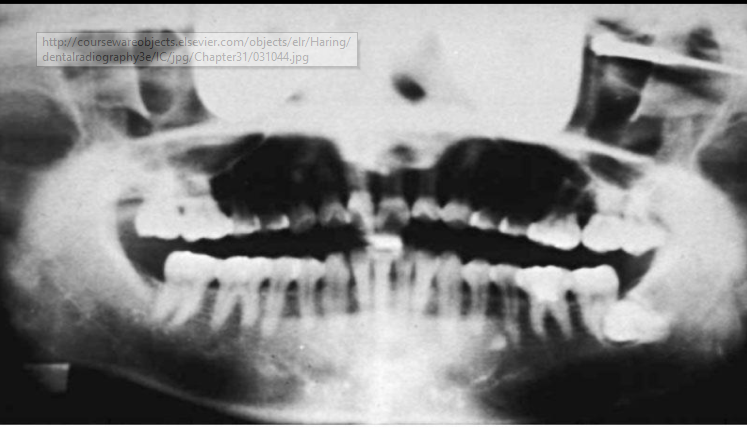

Describe Rampant caries.

Rampant caries refers to growing or spreading caries.

Advanced and severe affecting numerous teeth (can happen to both primary and permanent dentition)

Happens in children with poor dietary habits, nursing bottle syndrome or in adults with xerostomia (dry mouth) due to mediations.

Can also be a secondary condition to chemo radiation therapyÂ